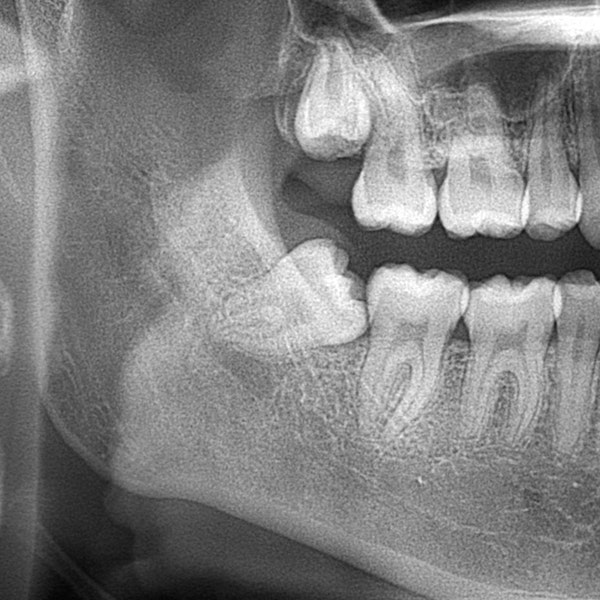

- Drs. Bill Stofer and Brock Spangle can handle simple and complex tooth extraction cases with gentle consideration. Whether you have an infected tooth that can't be saved or wisdom teeth that are causing problems, we can help.

The Tooth Extraction Process From Start to Finish